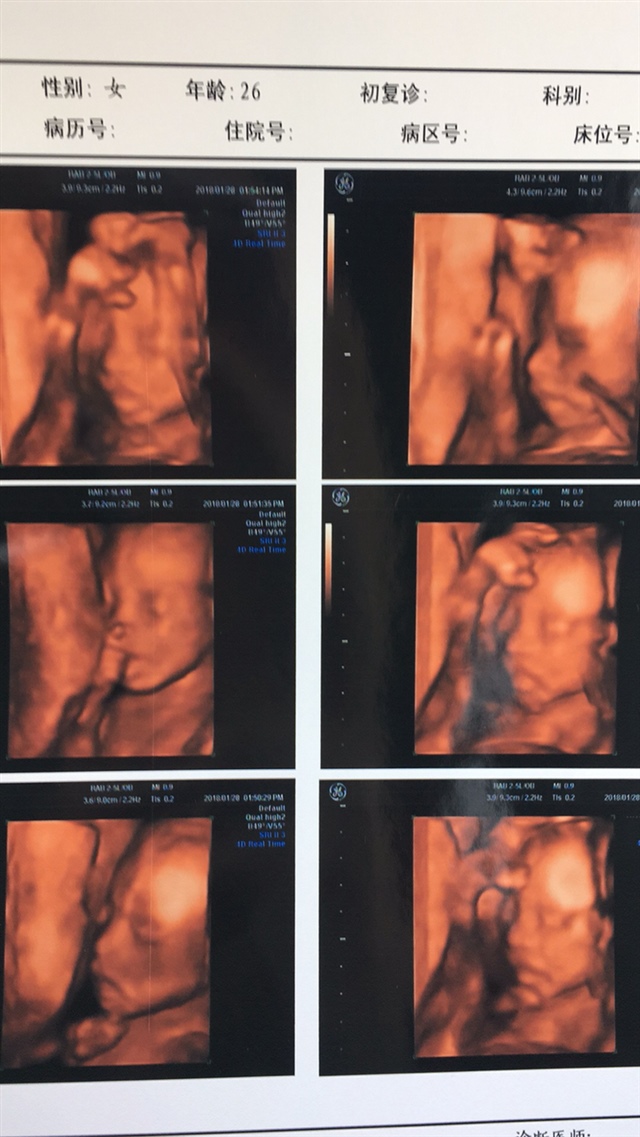

孕20周+1天

真好看

🌷🌸Ms.董🦄🍬[帖主]:都说是男孩

金晨:你做过四维彩超,他们应该暗示你性别了吧?

医生好好啊拍了这么多照片,我怀大宝的时候医生就拍了一张照片还不让看电脑

🌷🌸Ms.董🦄🍬[帖主]:躺在那里看的是投影 有一些是我自己拍的

宝宝允吸自己手手的图片太可爱了,好神奇。